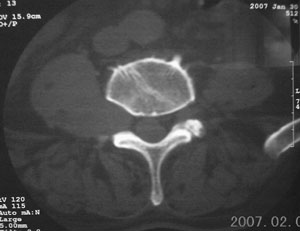

标题: CT8116:帮忙看这侧隐窝里是什么?男,75岁,腰周疼5-6年 [打印本页]

标题: CT8116:帮忙看这侧隐窝里是什么?男,75岁,腰周疼5-6年

男,75岁,腰周疼5-6年。别无症状。

考虑神经源性肿瘤可能大。依据:右侧神经孔扩大,相应部椎体压迫吸收。建议增强扫描,或mri平扫+增强。t1呈低等信号,t2呈高信号。增强后病灶(+++)强化。病灶内常见坏死。

右侧椎旁、侧隐窝软组织肿块,呈不规则双极征改变,椎体后外缘骨质弧形压迹,椎间孔扩大;考虑神经源性肿瘤,神经鞘瘤可能性大,需与神经纤维瘤相鉴别。

病变侧椎间孔扩大,椎体缘受压吸收;

考虑神经源性肿瘤,神经鞘瘤可能;

病变侧椎间孔扩大,椎体缘受压吸收,考虑神经源性肿瘤(神经鞘瘤可能)。